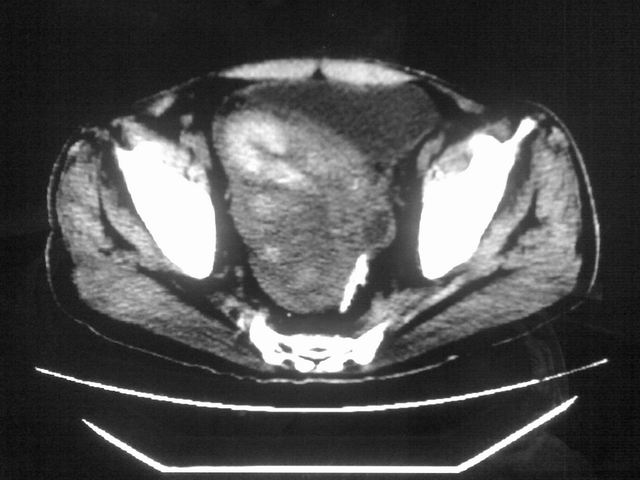

患者m 56岁,盆腔及下腹部胀痛半年,加重1月余,消瘦\中重度贫血.(附:平扫时直肠的高信号为,残留的钡剂).补一下病史:胃镜及纤维结肠镜均无明显异常.

首先是病灶的定位,平扫看很象肠管肿瘤但既然纤维结肠镜正常就可以除外结肠病变,增强成不均匀强化,位于右下腹部应该首先考虑回肠末段占位性病变,1淋巴瘤,2间质瘤,3腹膜后神经原肿瘤待除外,

膀胱后方及直肠前方见巨大混杂密度影,与前列腺相连且向膀胱内突入,精囊腺显示不清;考虑前列腺癌侵犯精囊、膀胱。

膀胱及直肠间有不规侧的软组织密度影,内密度不均匀。其内有坏死囊变,前列腺及精囊腺,膀胱后壁受浸。结合病史考虑腹膜后肉瘤可能性大。